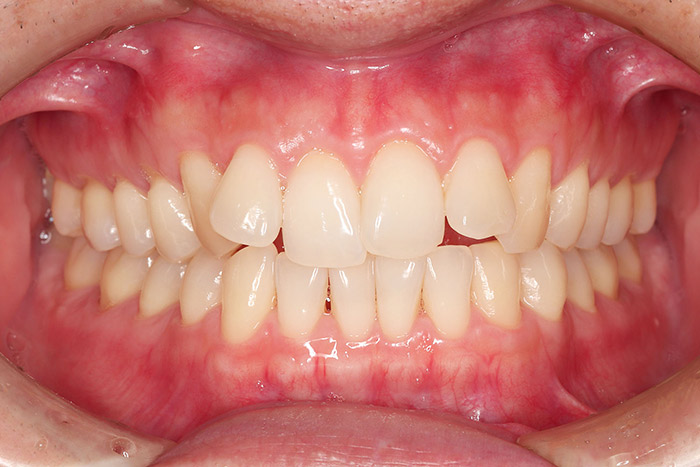

治療後

after

患者の症状 叢生、正中のずれ、上顎左右側切歯の口蓋側転位(交叉咬合)

治療方法 非抜歯で、マウスピース型カスタムメイド矯正歯科装置(インビザライン)による矯正

歯列弓を拡大することで非抜歯を可能にしました。

治療結果 側切歯の交叉咬合は解消、上下正中のずれも改善し咬み合わせが良くなりました。